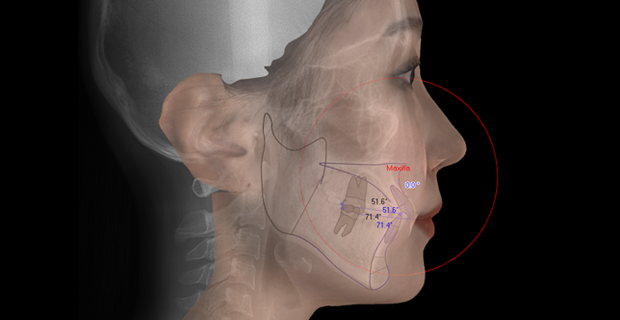

3D 디지털 정밀진단시스템

아이테로 루미나, 모르페우스, 본에이지 성장판 검사 등

첨단 장비를 도입해 진단부터 치료 계획까지

전 과정을 디지털화 했습니다.

3차원 분석은 물론, AI 기반 뼈 나이 판독으로

성장단계에 따른 최적의 치료 시점을 제시합니다.

• Cephalometric X-ray 촬영

2~3초의 짧은 시간 안에

얼굴의 측면 엑스레이 촬영이 가능합니다.

• 3D CBCT 촬영

낮은 방사선량으로 파노라마 이미지와

CT 이미지를 한번의 촬영으로 동시에 얻을 수 있습니다.

• Morpheus 3D 촬영

3D 얼굴 스캔으로 얼굴형, 비대칭 정도, 얼굴의 비율 등을 측정하며,

교정 치료 후 변화된 모습을 바로 시뮬레이션할 수 있습니다.